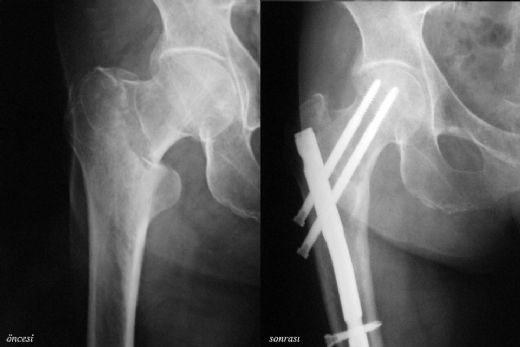

Kalça Röntgeni Nasıl Yorumlanır? Hangi Bulgular Önemlidir?Kalça röntgeni, kalça eklemi ve çevresindeki yapıların değerlendirilmesi için sıklıkla kullanılan bir görüntüleme yöntemidir. Bu görüntüleme, çeşitli ortopedik ve romatolojik durumların tanısında önemli bir rol oynar. Röntgen filmlerinin yorumlanması, klinik pratiğin vazgeçilmez bir parçasıdır ve sağlık profesyonellerinin doğru bir değerlendirme yapabilmesi için belirli standartlara uyması gerekmektedir. Röntgen Çekimi ve Pozisyonlama Röntgen çekimi, genellikle iki temel pozisyonda gerçekleştirilir: anterior-posterior (AP) ve lateral pozisyon.

Patolojik Bulgular: Osteoartrit bulguları röntgende genellikle femur başında ve asetabulumda kireçlenme, eklem aralığında daralma, osteofit oluşumu ve subkondral skleroz olarak belirginleşir. Fraktür durumlarında, kemik bütünlüğünde bozulma ve yer değiştirmeler gözlemlenebilirken, displazide ise eklem yapısının anormal gelişimi dikkat çeker.